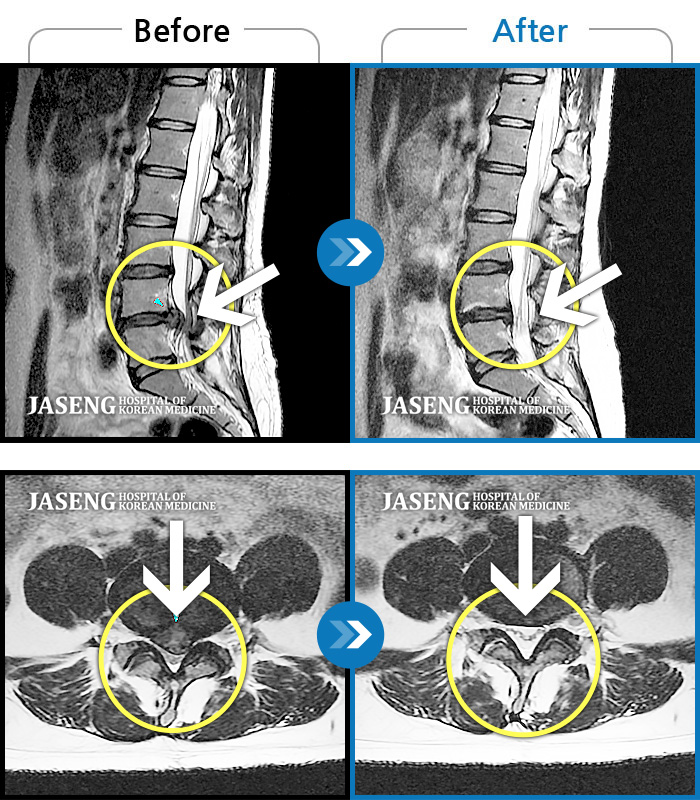

허리디스크

보라매 · 왕오호 원장

허리 통증, 똑바로 서려고 하거나 걸을 때 양쪽 허벅지와 고관절 시큰거림

촬영시기

2017.06.07 ~ 2018.04.17

2018.12.28

조회수 4,169